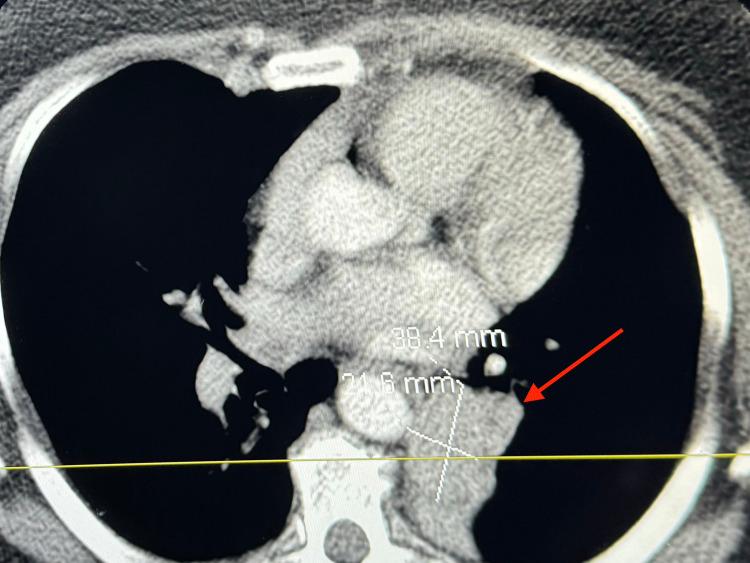

Endobronchial carcinoid tumors, a subset of neuroendocrine tumors, represent a rare but significant entity within pulmonary neoplasms, constituting less than 2% of all lung cancers. Our case report details the clinical presentation, diagnosis, and management of a 56-year-old female patient who presented with intermittent wheezing, mucoid cough, and recurrent pneumonia. Initial imaging and bronchoscopy identified an obstructive mass in the left lower bronchus. Histopathological examination of the bronchoscopic biopsy confirmed the diagnosis of a typical endobronchial carcinoid tumor. The patient underwent a successful left lower lobe lobectomy of the lung through left thoracotomy with regional and mediastinal lymph node dissection. Follow-up evaluations demonstrated no recurrence post-treatment. This case highlights the clinical features, diagnostic challenges, and therapeutic strategies associated with endobronchial carcinoid tumors, emphasizing the efficacy of a multidisciplinary approach in achieving favorable outcomes.